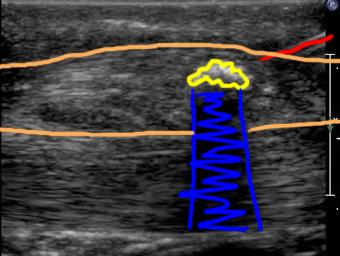

Ultrasound is a bit like fluoroscopy, in that during the actual exam, the operator sees what is going on in real-time, and captures selected images to show what they saw. This image series shows a needle being inserted into the left Achilles tendon, to break up some calcification that has formed there, and relieve pain. A labeled image is shown below the movie to help figure out what is going on. US images take practice to interpret because they are low resolution (not much detail). The best view of what is going on is obtained by the operator who sees everything in real-time, as it happens.

Because US is a real-time exam, it is ideal for guiding procedures, since you can watch where the needle throughout the entire procedure.

yellow=calcium deposit; blue=blocked beam beyond the calcium (which acts like a bone); red=needle; orange=Achilles tendon